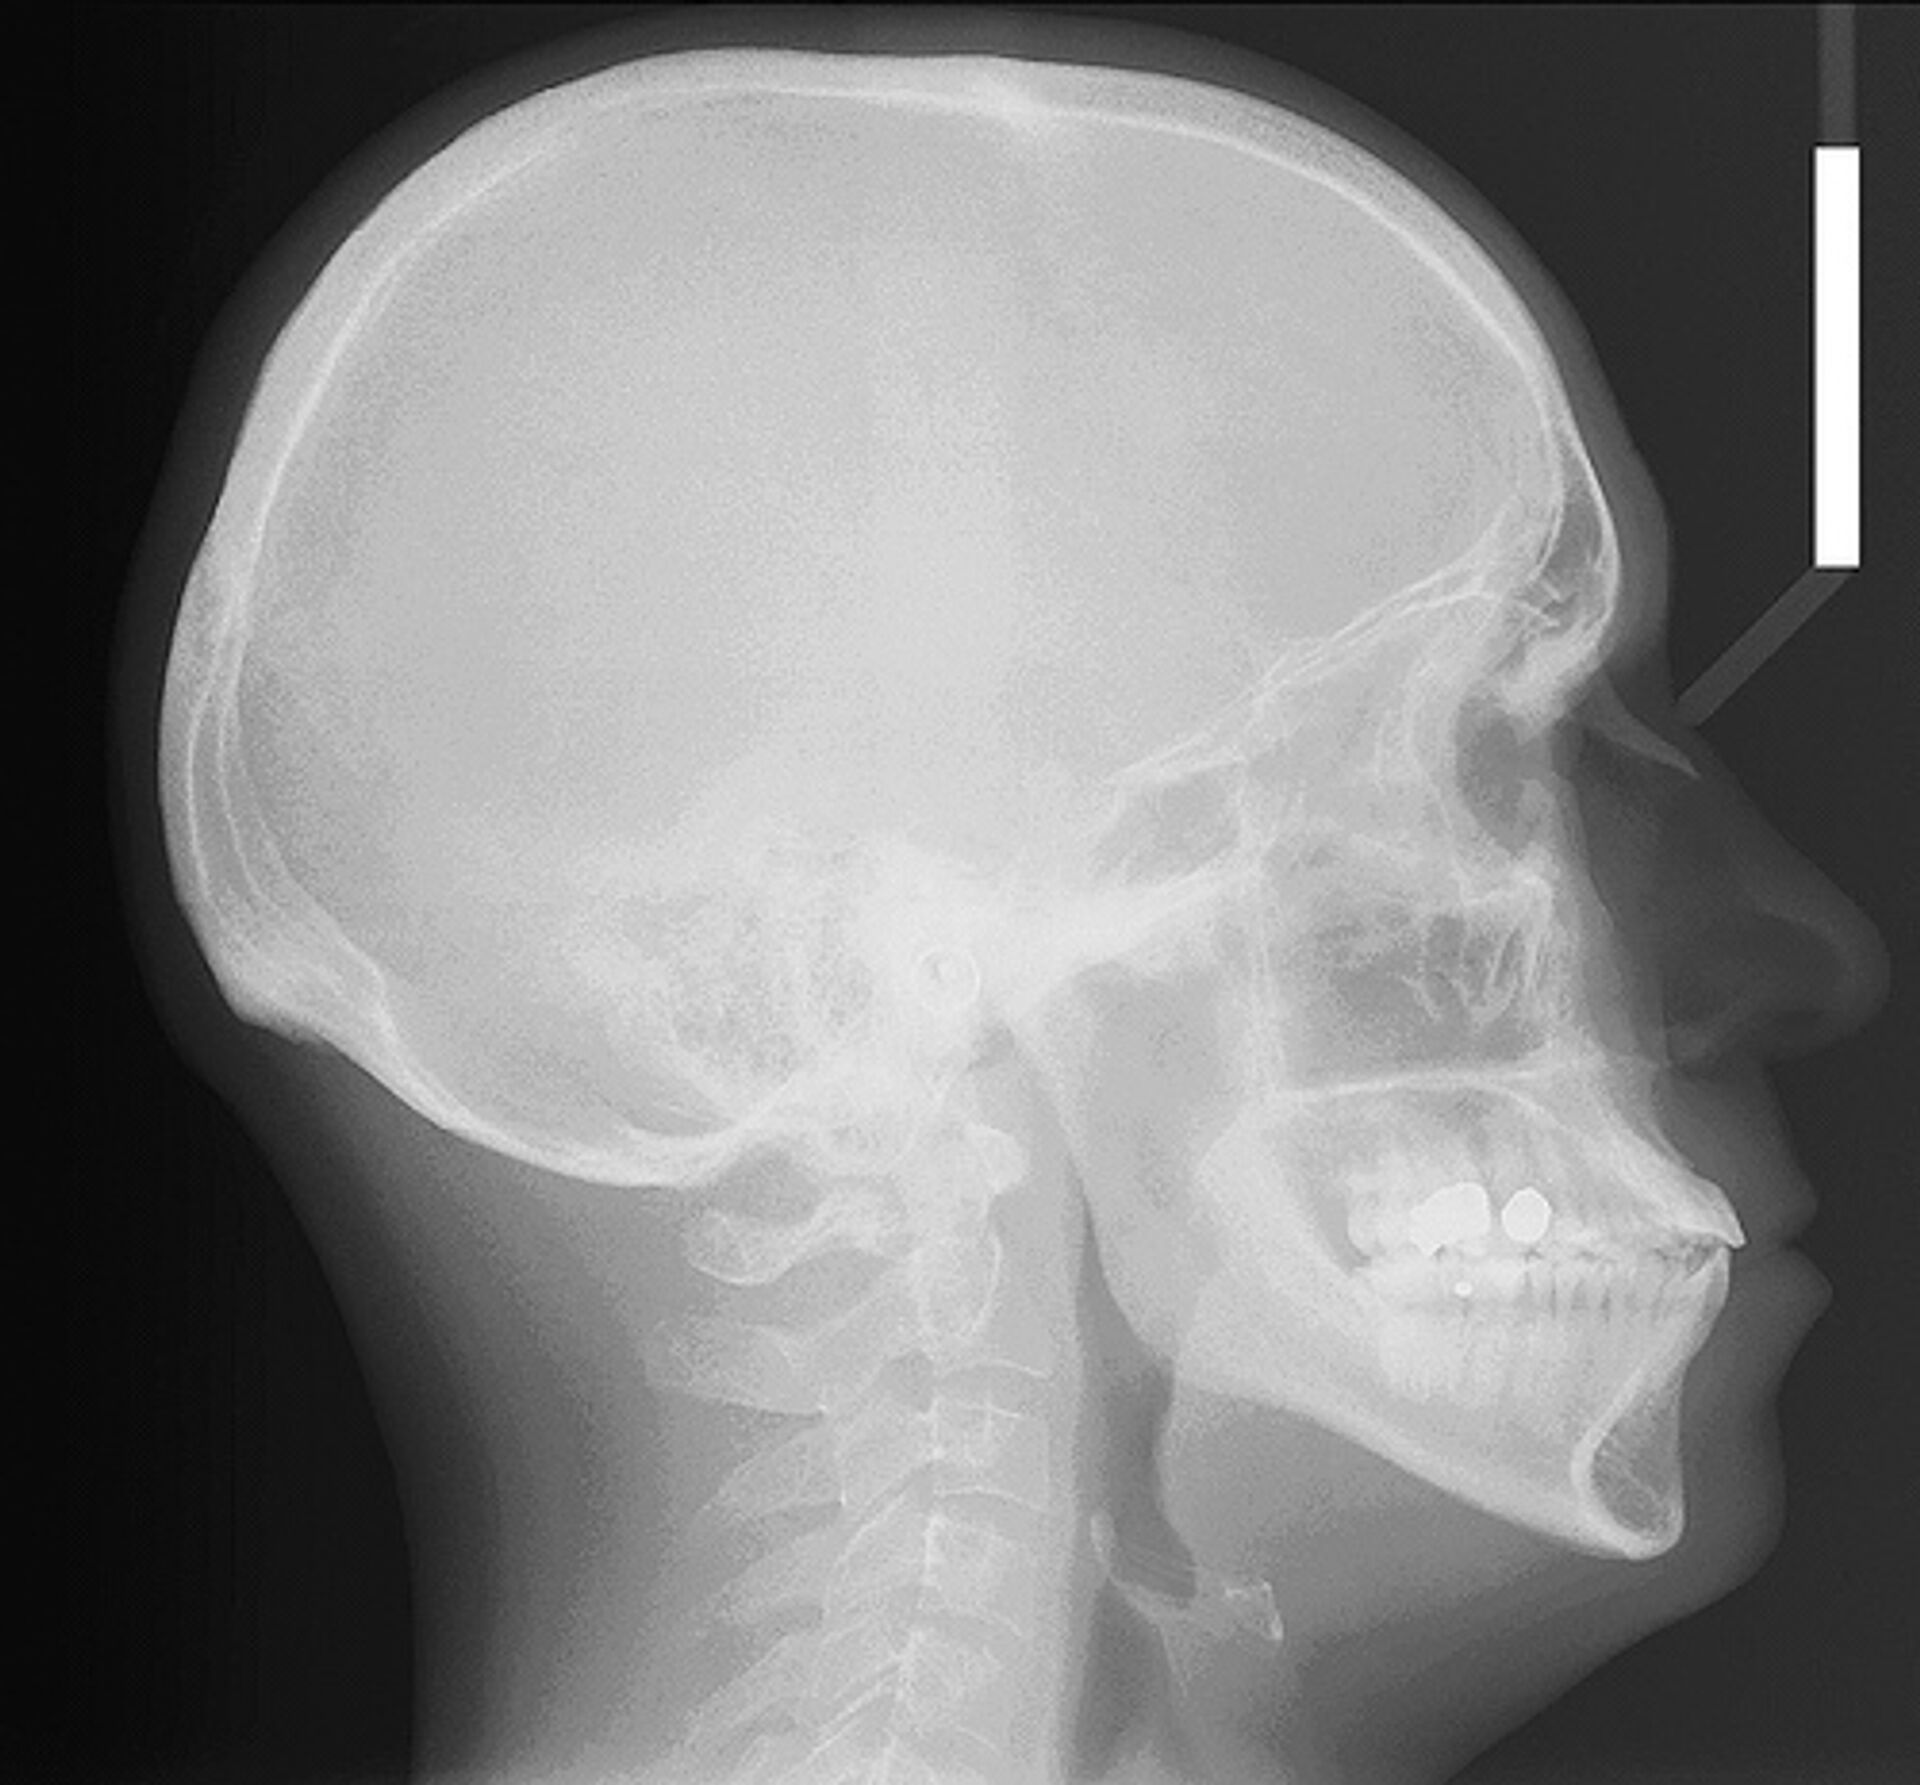

Una sexagenaria china vivió ocho meses con un palo de bambú de 12 centímetros en la cabeza.

La operación quirúrgica para extirpar el cuerpo ajeno de la cabeza de la paciente transcurrió sin complicaciones, según fuentes médicas, que no supieron responder cómo el palo llegó a parar al cráneo de la mujer.